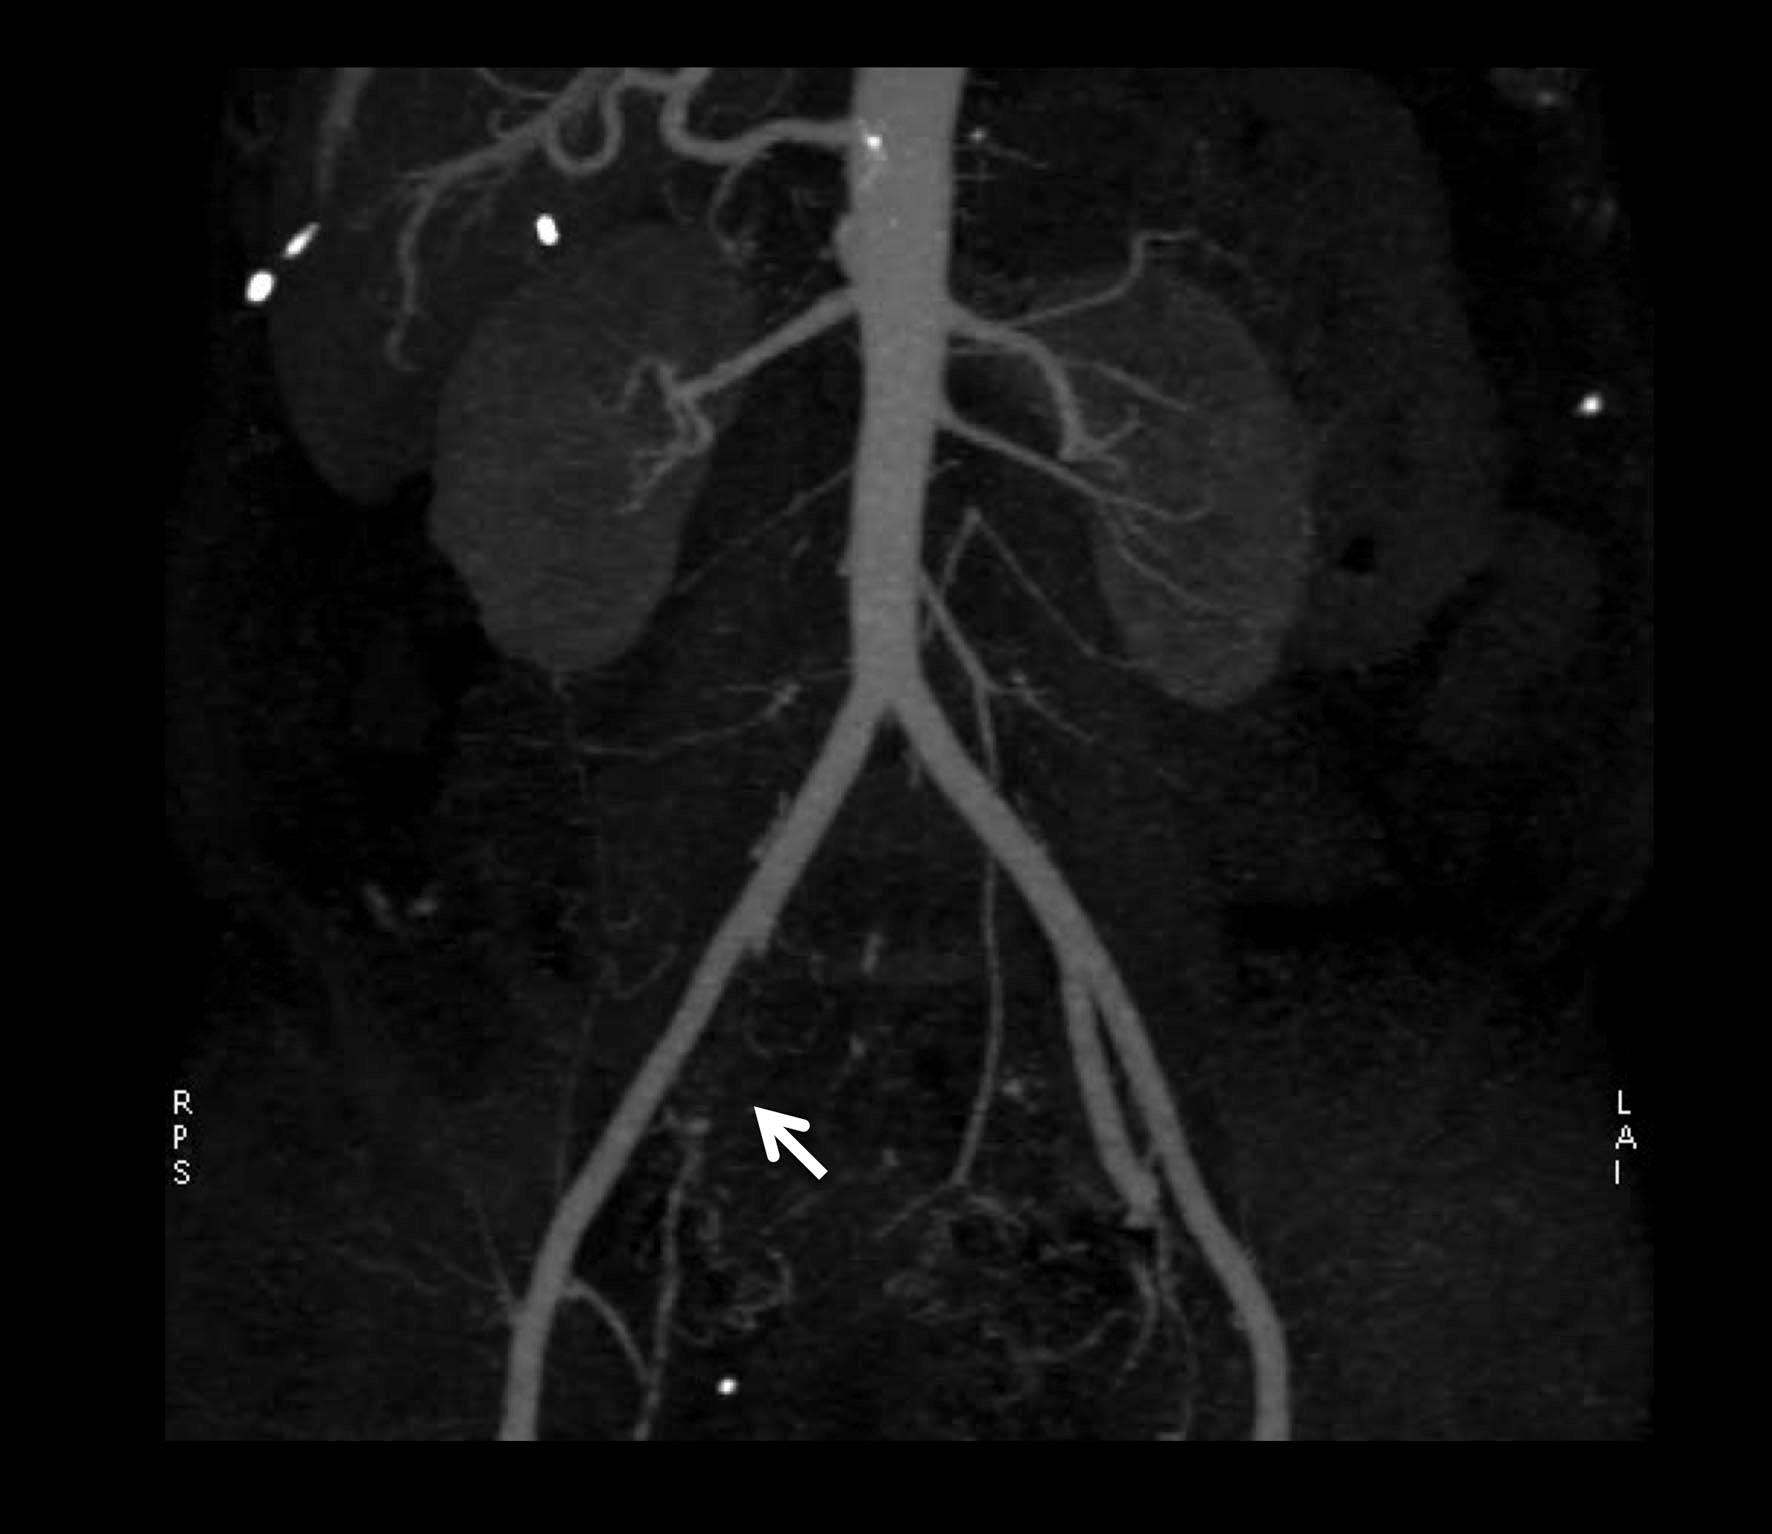

Computerized-tomodensitometric angiography (CTA) and magnetic-resonance angiography (MRA), “semi-invasive” exams, can be an option for the diagnosis of IIAS especially when a patient is candidate for revascularization (Figure 2) (11).

Figure 2. Results of computerized-tomodensitometric angiography: occlusion of the right internal iliac artery. Arrow, occlusion of the right internal iliac artery.